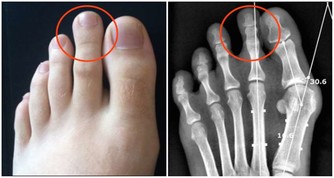

通常,我們不需要仔細觀察自己的十指,只要單獨觀察食指就可以了。

1、看顏色正常的指甲顏色是肉色的,如果我們的食指指甲發白的話,

那就說明我們的肝血並不是特別旺盛,已經出現了肝血虛的症狀。

如果我們的指甲顏色是暗黃色的,那就很可能是肝膽疾病的先兆。

2、看紋路一般來說,食指的指甲上是很少會出現紋路的。如果我們的指甲上出現了橫溝,那說明肝臟的營養不良。

而指甲上出現了縱紋,那就說明最近的身體比較虛弱,我們一定要注意休息。

3、看斑點身體健康,指甲上是不會出現任何斑點的。如果食指的指甲上出現白色的斑點,說明我們的肝臟機能出現了損傷。

如果指甲的下方出現了紅色斑點,說明肝血循環不暢,肝臟甚至有病變的可能。